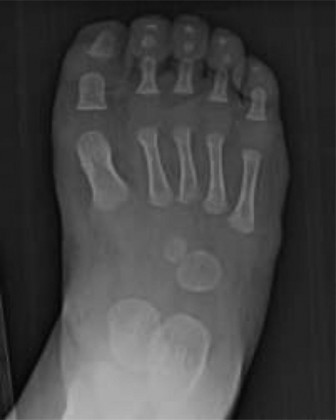

This is a hallmark feature, ranging from hypoplasia or absence of the 4th and 5th toes (often referred to as 'lateral ray deficiency') to a more extensive oligodactyly involving additional rays.

Pappas's classification, which delineates eight grades based on the extent of fibular involvement and associated tibial bowing, also provides valuable insights into the variability of this condition. Key pathological features universally observed include progressive LLD, anterior-medial bowing of the tibia, ankle valgus (often with talar hypoplasia or dysplasia), and hypoplasia or agenesis of the lateral rays of the foot, frequently involving the 4th and 5th toes, or more extensive oligodactyly. The overarching therapeutic challenge lies in restoring functional limb length, achieving mechanical alignment, and ensuring a plantigrade, stable foot for independent ambulation.

This is a hallmark feature, encompassing hypoplasia, aplasia, or absence of the lateral-most rays, most commonly the 4th and 5th toes. More extensive oligodactyly involving additional rays can also occur. This directly impacts foot width and stability.